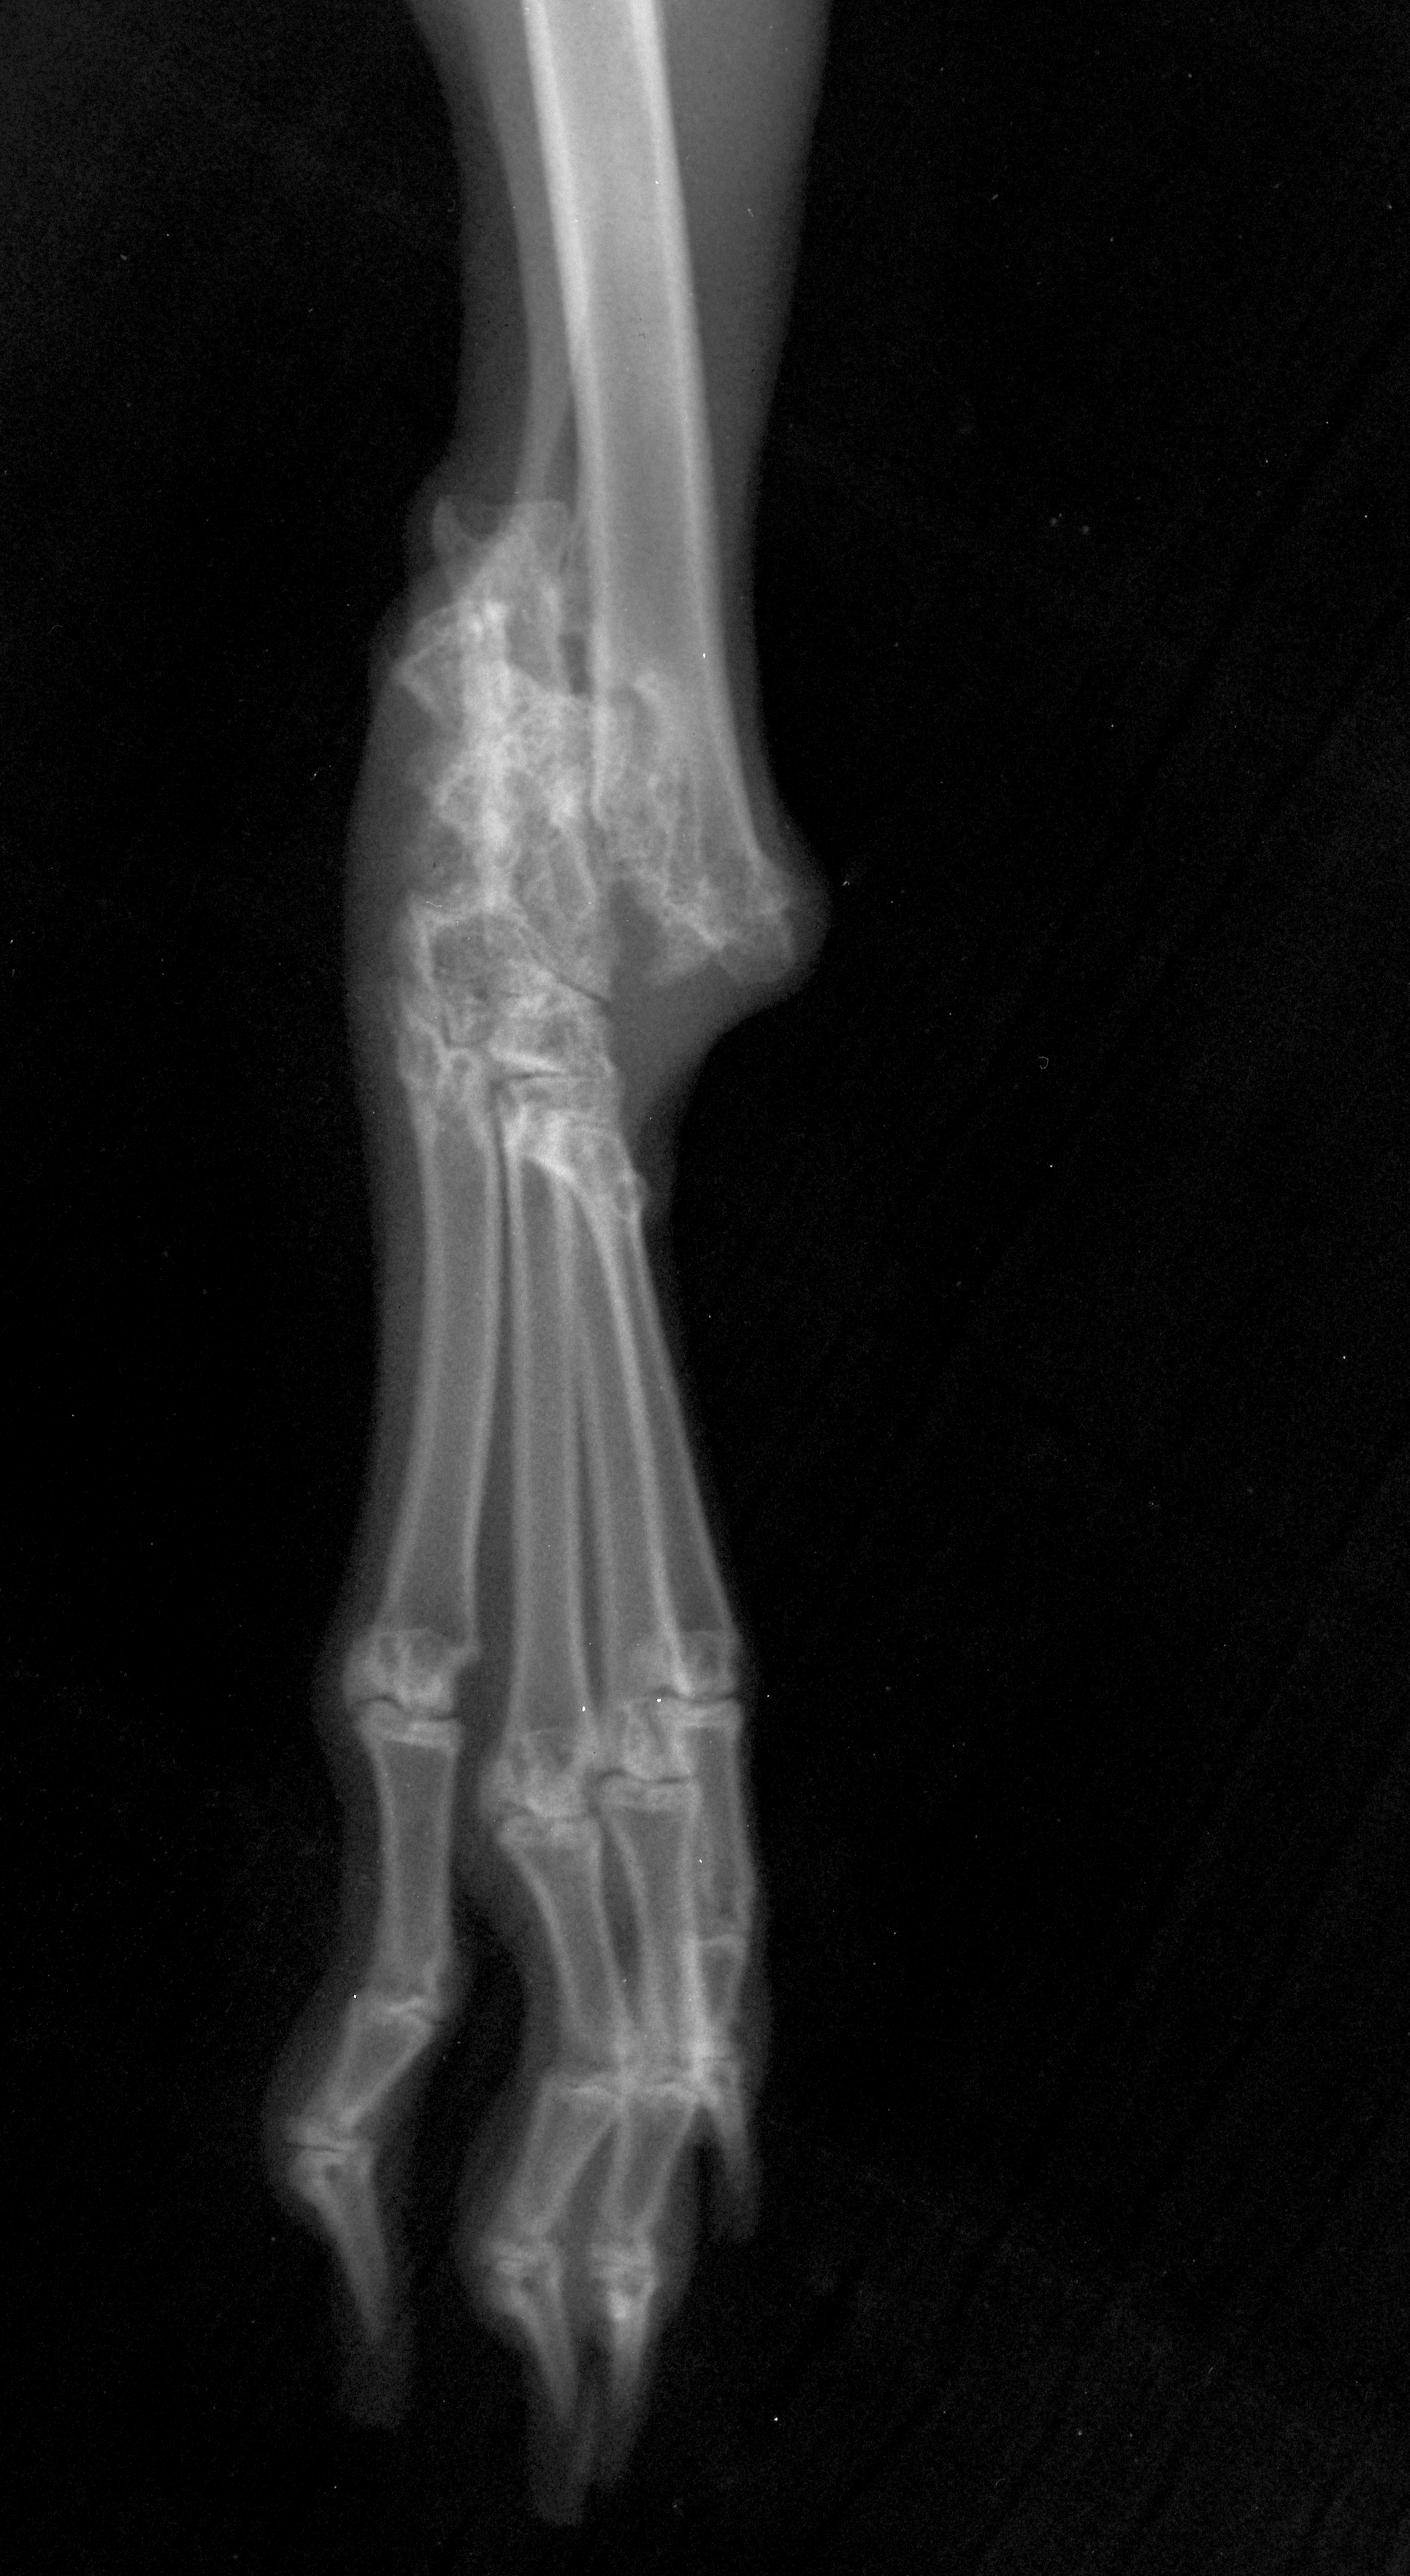

Jack VD fractured hock